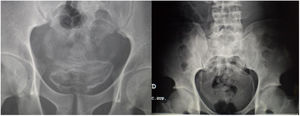

Las exploraciones radiológicas desempeñan un papel importante en el diagnóstico de la enfermedad y sus complicaciones9,29. La radiografía de abdomen puede mostrar principalmente calcificaciones en la pared de la vejiga (fig. 4). La ecografía es la exploración más rentable, permitiendo diagnosticar lesiones en vejiga urinaria como engrosamientos de la mucosa, nódulos (fig. 5), ureterohidronefrosis o la fibrosis periportal (fig. 6) con o sin hipertensión portal característica de la afectación hepatointestinal. Otras exploraciones como la TAC o la RMN pueden ayudar al diagnóstico, sobre todo en casos de localizaciones ectópicas como puede ser el pulmón o el sistema nervioso central. La tabla 2 muestra resumidas las características de las principales pruebas empleadas en el diagnóstico de la esquistosomiasis.